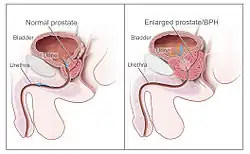

| Diagram of a normal prostate (left) and benign prostatic hyperplasia (right) | |